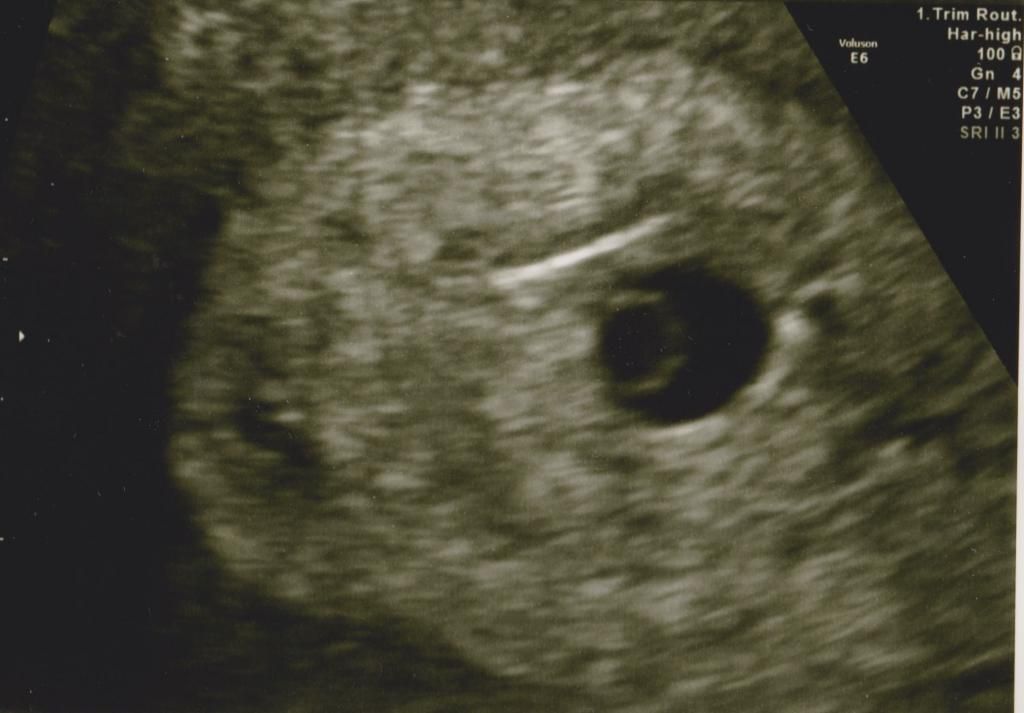

Geen baby te zien op echo- alleen vruchtzakkie en dooier...de gyn bevestig wel dat ik zwanger was- alleen misschien te vroeg om embrio te zien. Volgens haar kan het niet anders dat ik nu pas 5 weke ver ben..dat snap ik niet..want volgens mijn ovulatie datum van 29 juni moet ik nu 6 weken ver zijn...als je uitga van mijn laatste menstruatie klopt het zowiezo niet- want mijn ovulatie was pas op CD 23 en dan moest ik nu al twee weken verder zijn... Maar hier op de foto duidelijk te zien- vruchtzakkie (groot sirkel) en dooier- (klein sirkel) Ik heb hier al gelezen over vrouwen waar wel een vruchtzakkie was..maar geen baby- ben bang dat het bij mij ook het geval is.Dat hoop ik natuurlijk niet- de gyn vroeg wel of ik bloeding had...dus ik voel me niet echt gerust.... Nu wachten tot de 11de Augustus voor de volgende echo- dan hopen we op een positief bericht.